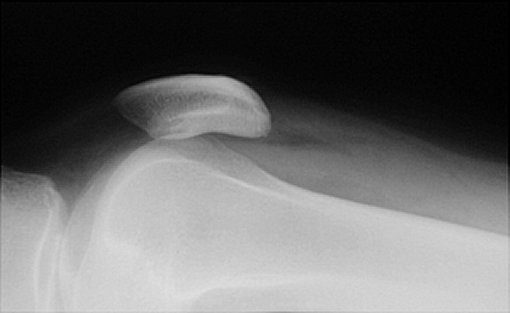

When there is an intraarticular fracture of the tibial plateau or of one of the femoral condyles, bone marrow (mostly fat) migrates from the marrow space into the joint space. With fracture, blood also escapes, and a lipohemarthrosis is produced. Fat is less dense than blood, and it layers superior to it, producing the change in radiographic density referred to as a fat-blood interface (FBI sign).

CASE 2: This radiograph is from a 52 year old male who was hit by a forklift. It is a cross table lateral view acquired in the emergency room. Click to enlarge.

CLICK TO ENLARGE